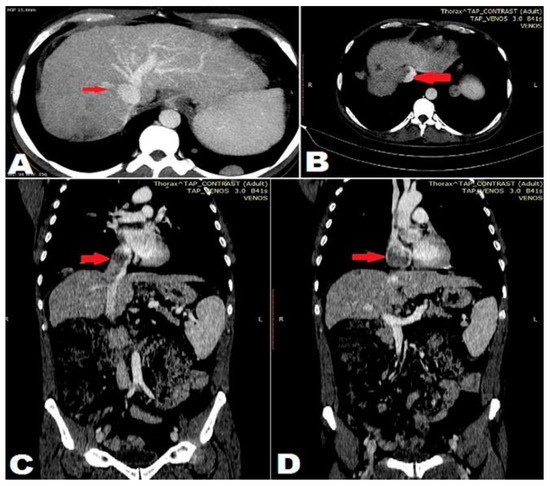

Hepatocarcinoma with Tumor Thrombus Occupying the Right Atrium and Portal Vein in a Patient with Hereditary Hemochromatosis and Liver Cirrhosis

Case report